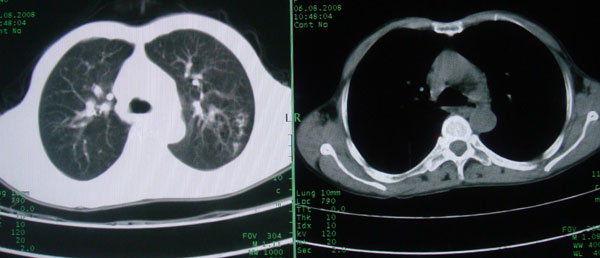

多考虑支气管扩张并感染,双下肺继发性肺结核不除外

周围型肺癌征象不明显,应不予首先考虑

考虑支气管肺泡癌可能性大

慢性支气管炎伴支气管扩张、感染,间质纤维化。

慢性支气管炎伴全小叶型肺气肿、支气管扩张、感染、间质纤维化